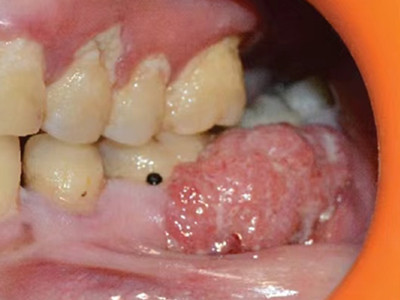

牙龈癌多源于牙间乳头及龈缘区,溃疡呈表浅、淡红,以后可出现增生。由于黏骨膜与牙槽突附着甚紧,较易早期侵犯牙槽突骨膜及骨质,进而出现牙松动,并可发生脱落。X线片可出现恶性肿瘤的破坏特征虫蚀状不规则吸收。

牙龈癌常发生继发感染,肿瘤伴以坏死组织,触之易出血。体积过大时可出现面部肿胀,浸润皮肤。